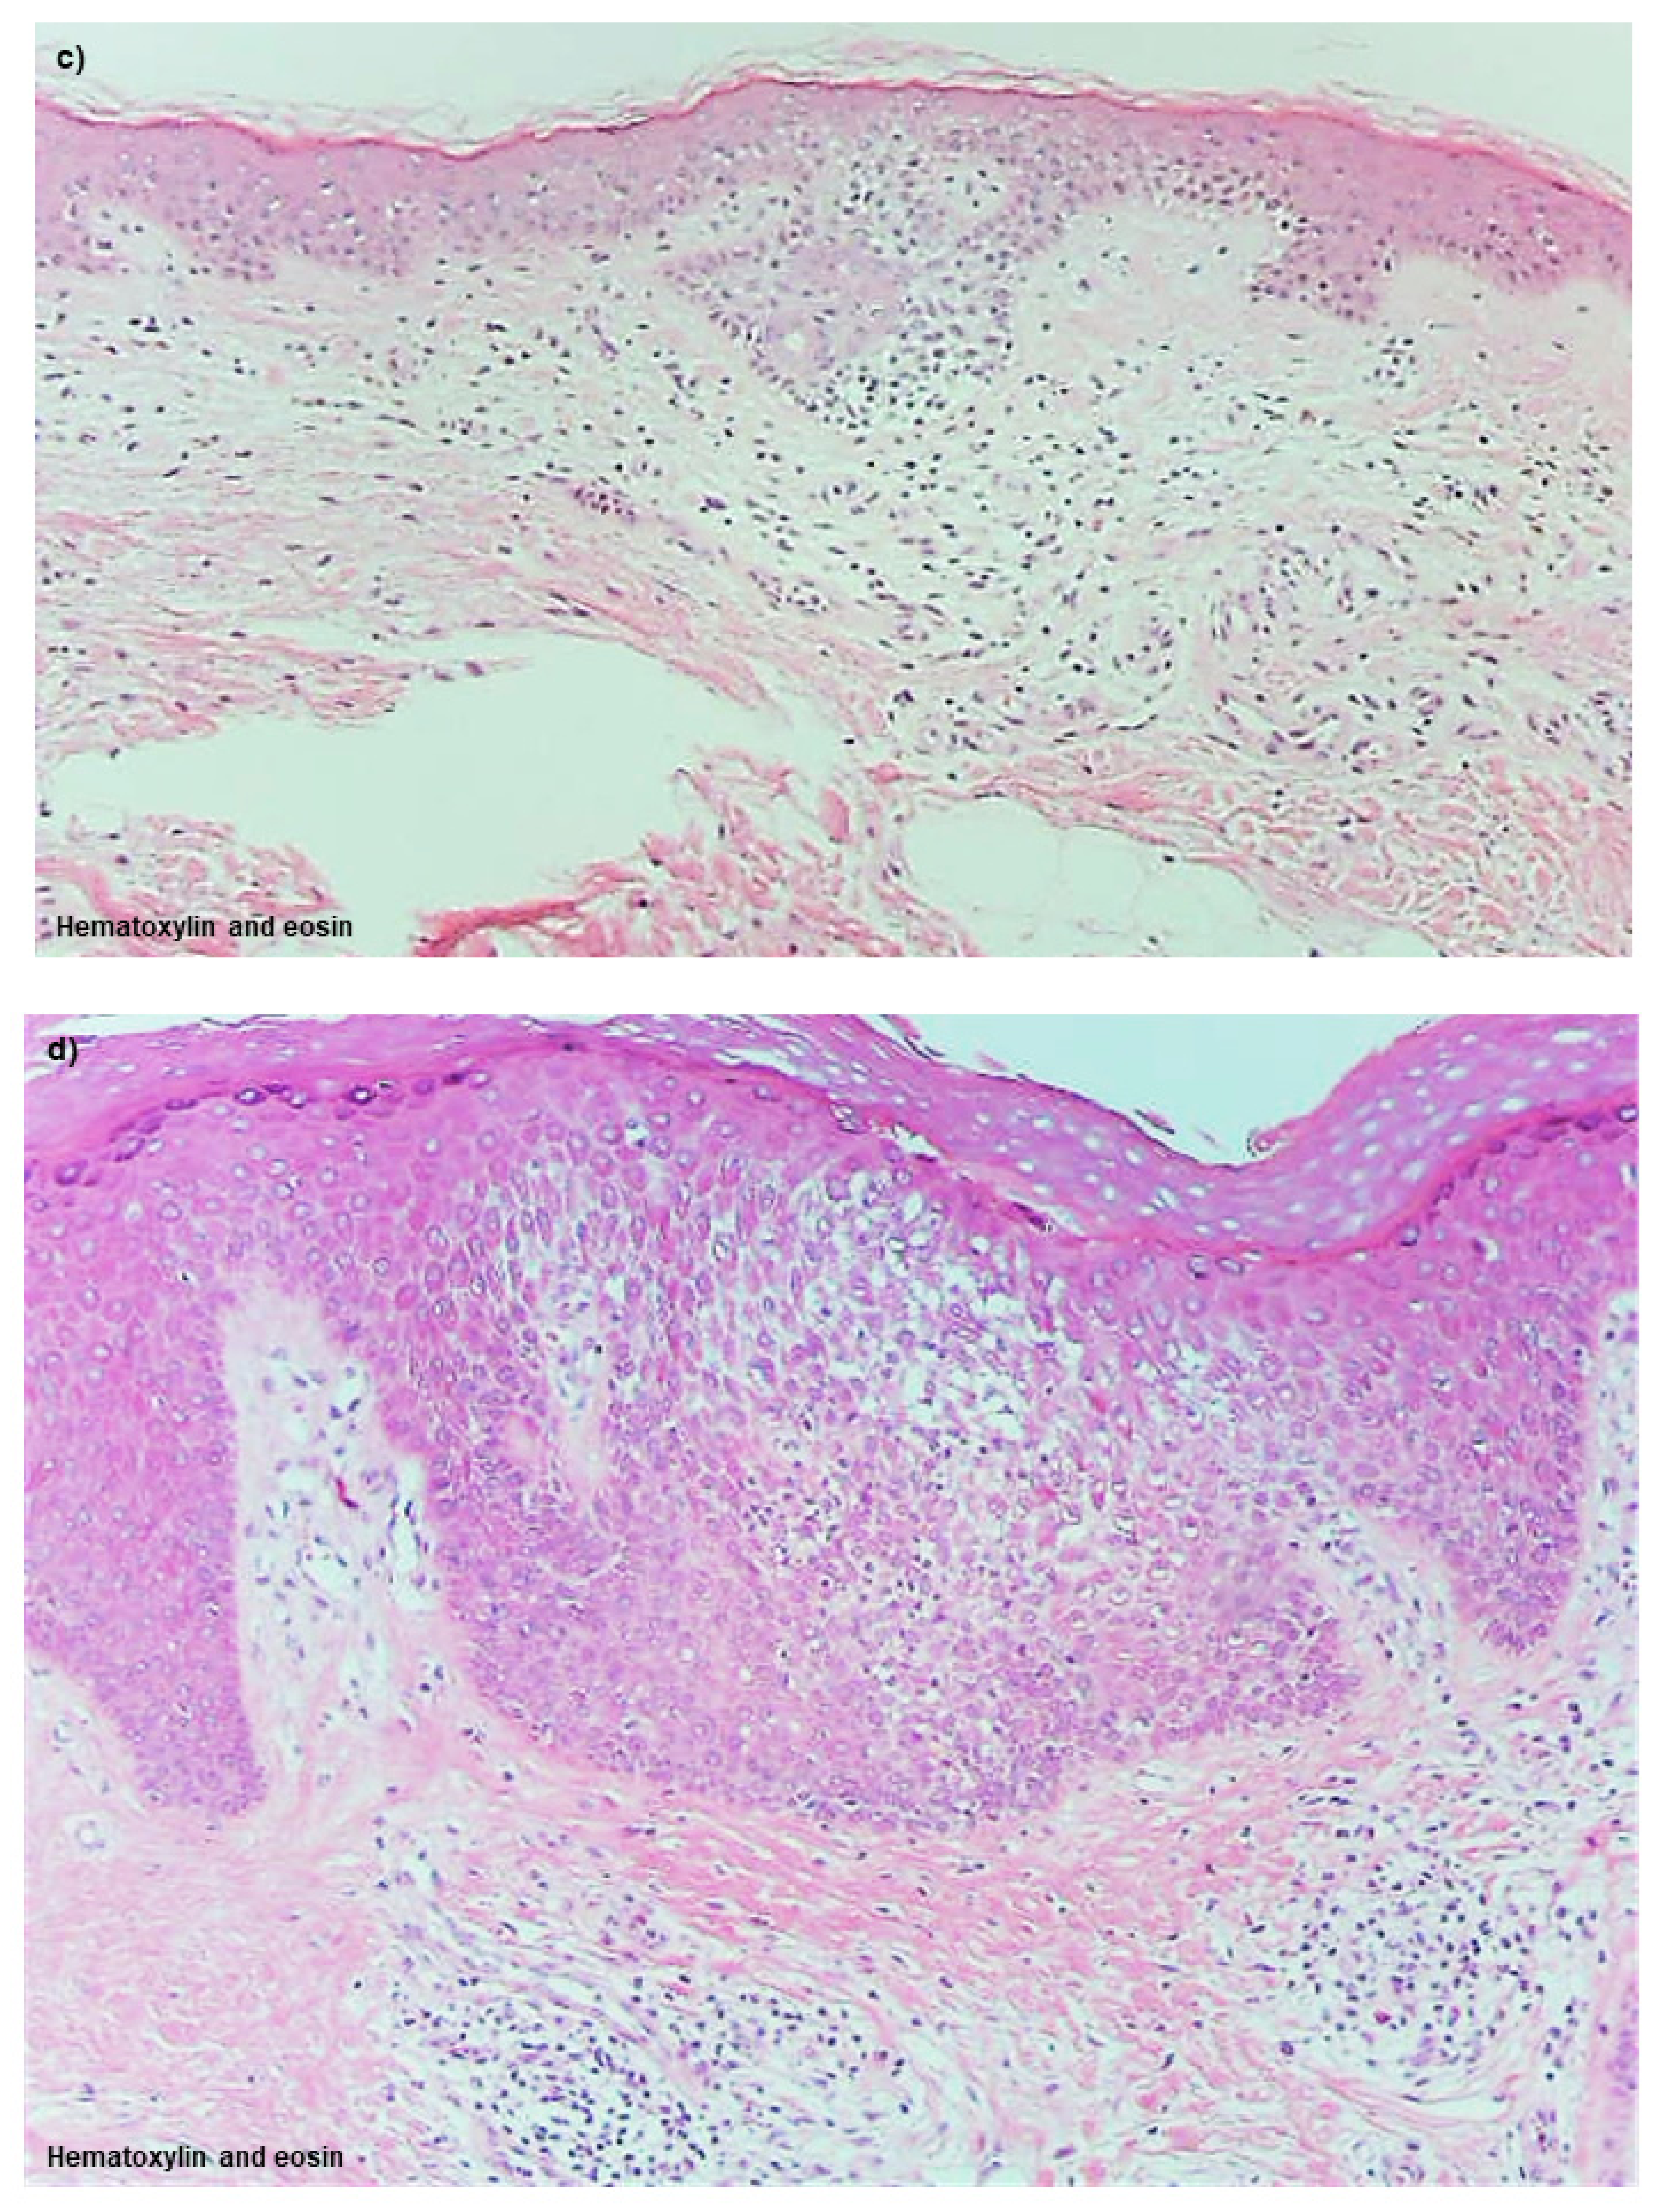

Uninvolved Skin

Non-Spongiotic Areas of Lichenified Eczema

Spongiotic Dermatitis in APT Positive-Reaction Sites

Spongiotic Dermatitis in Lichenified Eczema